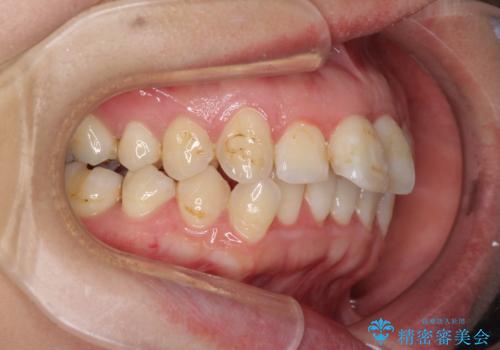

- 出っ歯と口の閉じにくさ、デコボコを気にして来院された患者様です。

口元の突出感を改善するため、上下左右第一小臼歯4本の抜歯を行い、ワイヤー装置による矯正治療を行うこととしました。

上下前歯の距離が大きかったため、上下の歯が接触するまでに時間がかかりました。

それでも目安である2年半で終えることができ、患者様には大変満足していただけました。